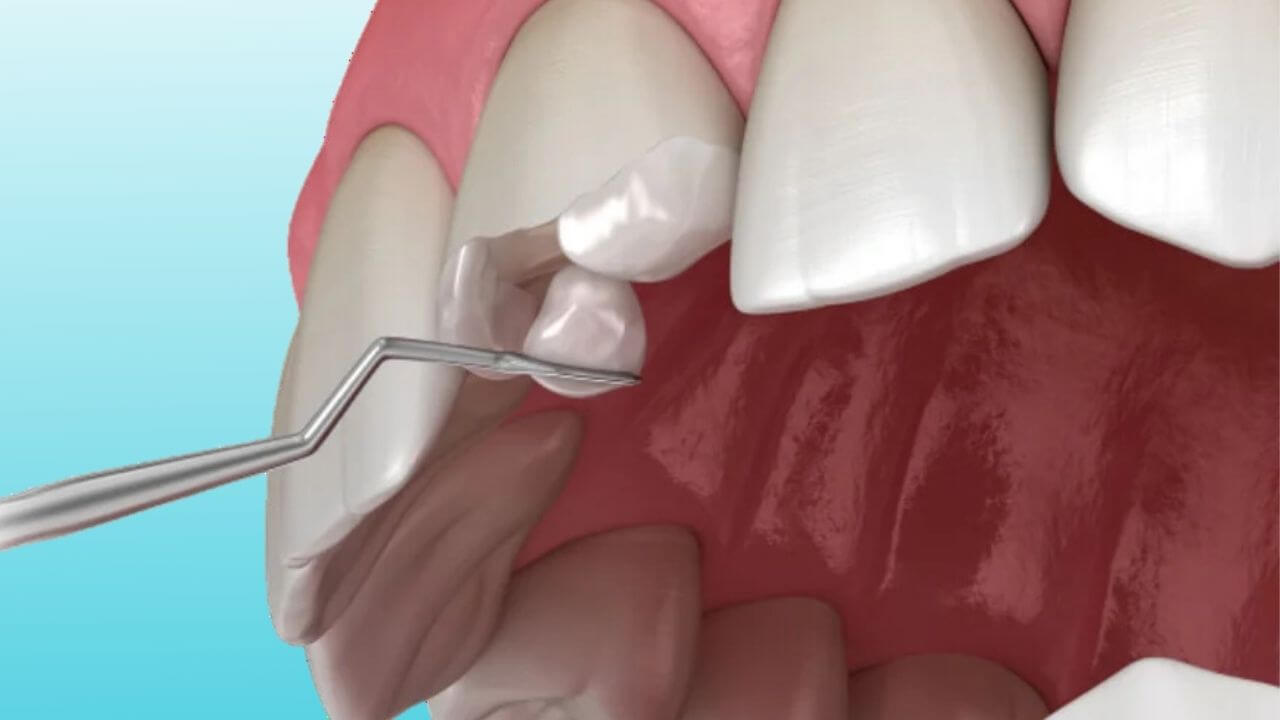

Painless Root Canal Treatment in Nashik | Care32 Dental Centre

Root canal treatment is often feared due to misconceptions about pain and discomfort. At Care32 D...

Painless Root Canal Treatment near College Road Nashik | Care 32

Discover the benefits of Painless Root Canal Treatment in College Road Nashik at Care 32 D...